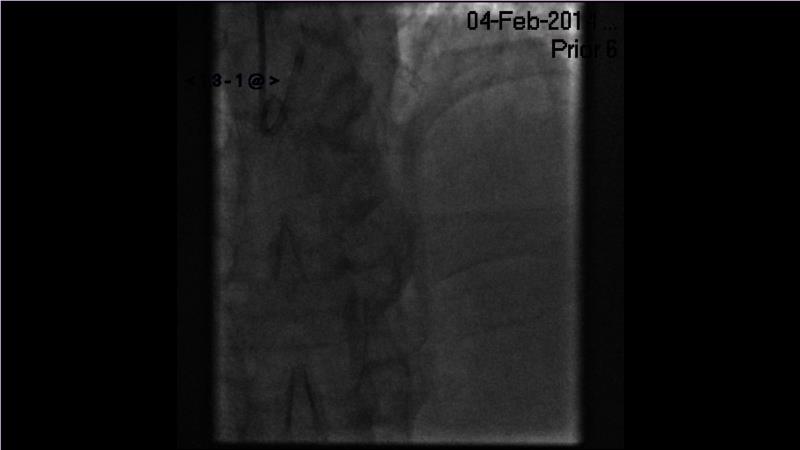

Browse this EuroPCR 2024 session to explore the safety and efficacy of sirolimus-coated balloons from pre-clinical data, review MagicTouch data from real-world populations with case-based examples, and learn about the MagicTouch sirolimus-coated balloon clinical programs. Discover insights and takeaways from the significance of the EASTBOURNE subgroups, and analyze the challenges and opportunities in PCI for diabetic patients.

- To learn from the real world registries and complex cases to understand the practical implications and potential of the device in diverse patient population